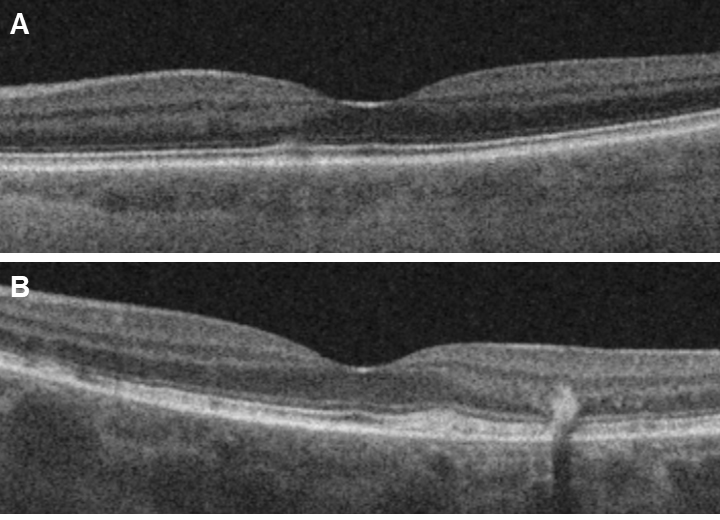

Figure 4. Optical coherence tomography. B-scans showing examples of A: mild changes with subtle outer retinal disruption (left eye of Subject 5) and B: alterations with more widespread outer retinal disruption (left eye of Subject 8) explained by the newly found additional

ABCA4 mutation.